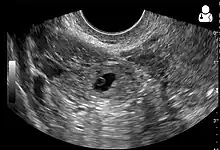

Ultrasound image showing an ectopic pregnancy where a gestational sac and fetus has been formed.